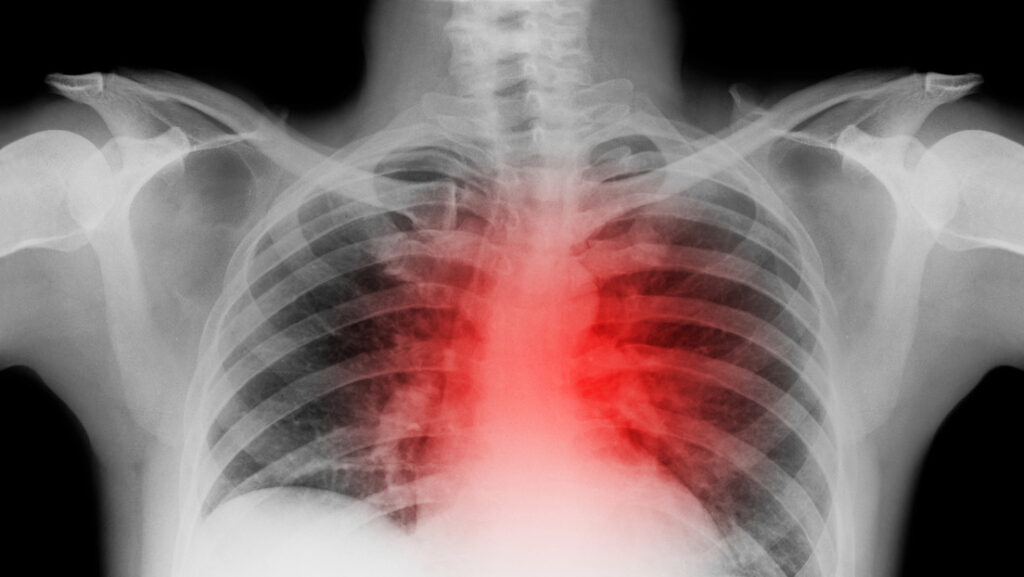

Tras la inesperada muerte de la leyenda estadounidense de la lucha libre Hulk Hogan a causa de una crisis cardíaca, se ha reavivado la conversación sobre cómo identificar los signos de un ataque al corazón para tratar de evitar un resultado fatal.

Inicialmente, hay que establecer la diferencia entre un paro cardíaco y un infarto. El primero, según la Clínica Cleveland, ocurre cuando el corazón deja de latir o late tan rápido que se detiene el bombeo de sangre. Por otro lado, un infarto se produce por una deficiencia en el flujo sanguíneo en una parte del músculo cardíaco, generalmente provocada por la obstrucción de una o más arterias del corazón. Aunque ambos pueden tener un efecto fatal, una respuesta inmediata y acertada puede salvar la vida del afectado.

Los síntomas de un paro cardíaco aparecen sin previo aviso, pero hay algunas señales que podrían ayudar a recibir el tratamiento adecuado.

De acuerdo con Irfan Asif, profesor de la Universidad de Alabama en Birmingham, “los signos típicos de un paro cardíaco incluyen pérdida repentina del conocimiento con ojos en blanco, actividad similar a una convulsión debido a la falta de flujo de oxígeno al cerebro y respiración irregular, dificultosa o nula”. Adicionalmente, el afectado podría tener un pulso muy débil o casi imperceptible.

Entre los síntomas previos al paro están la debilidad, palpitaciones y molestias en el pecho, así como dificultad para respirar. No obstante, sigue siendo un episodio difícil de anticipar, por lo que la respuesta es primordial.

Anualmente, la muerte súbita cardíaca se cobra en promedio entre 4 y 5 millones de vidas. Debido a que se trata de un problema eléctrico del corazón, puede ocurrir a cualquier edad, incluso durante la infancia. Los casos suelen ser más comunes entre los hombres, mientras que las mujeres tienen un riesgo mayor después de la menopausia.